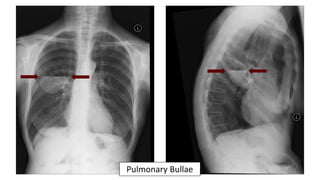

Pulmonary Bullae